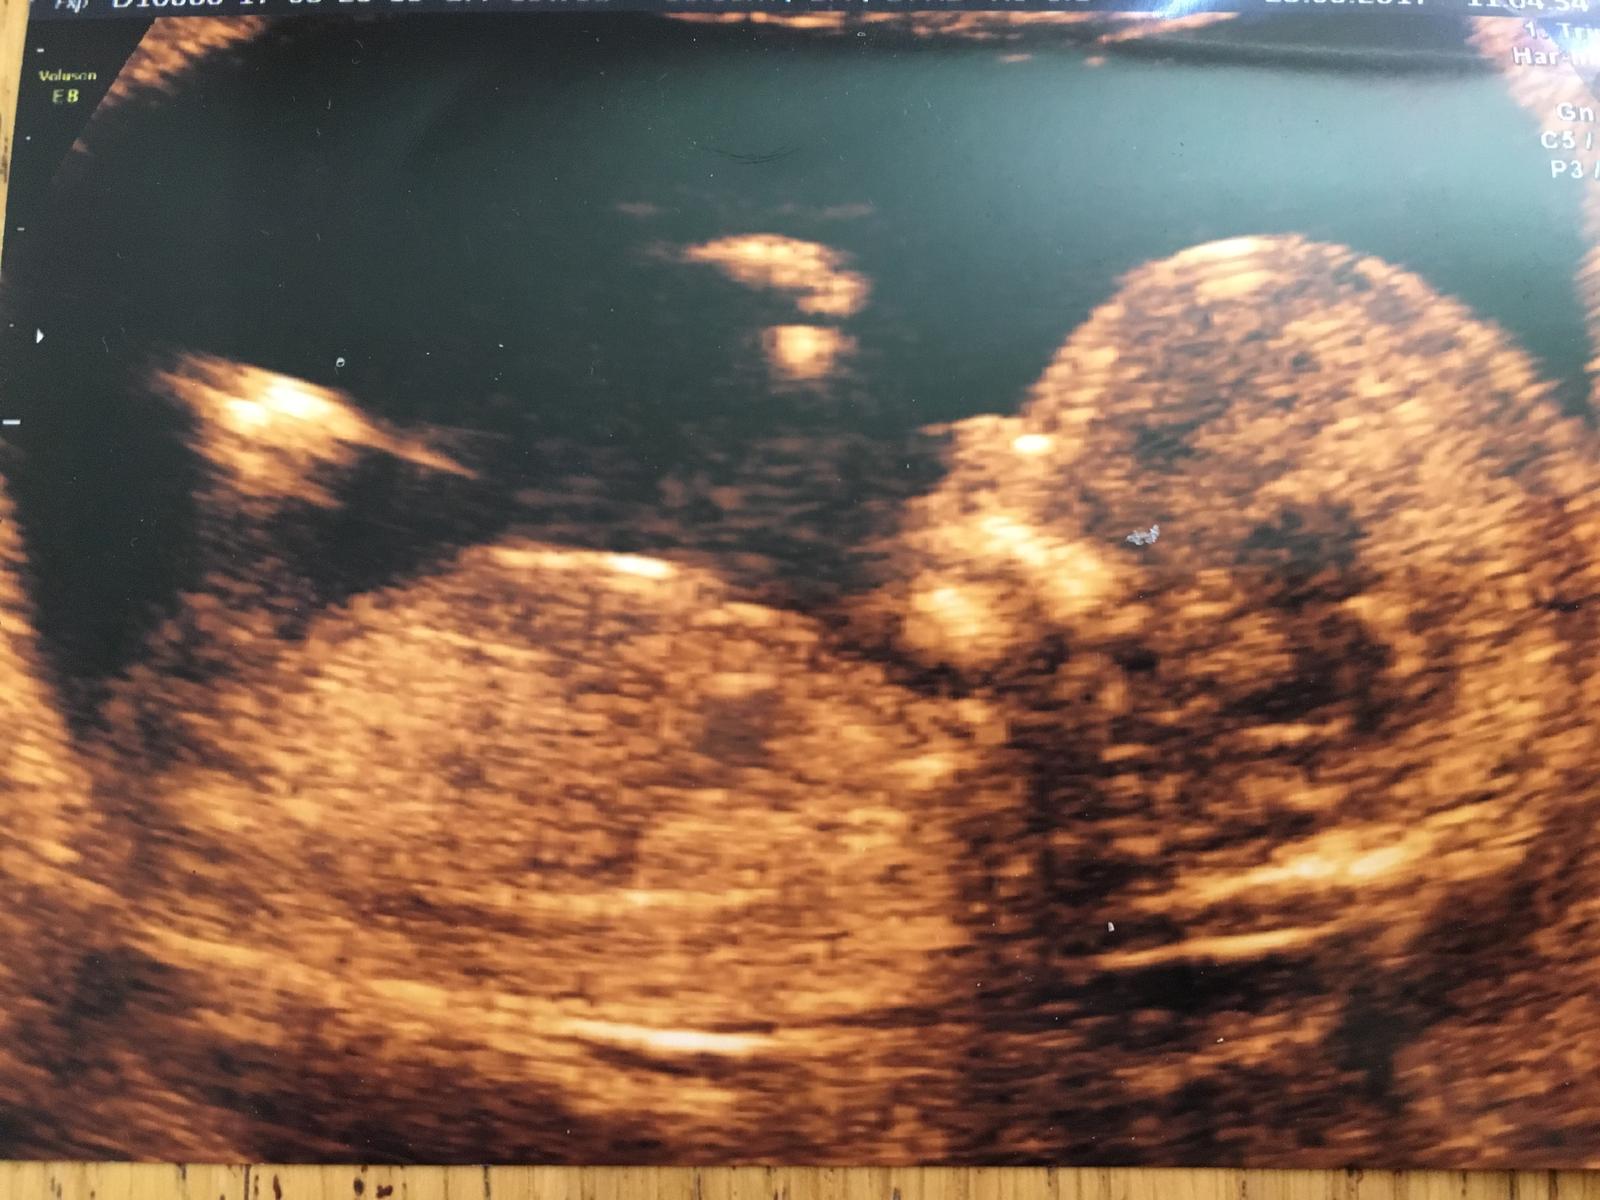

Je to holčička nebo chlapeček? Foto ultrazvuku

Moc bych si přála holčičku, mám doma dva kluky. Uvidím na dalším ultrazvuku a budu se těšit

@verinikki Me treba rekli kluk a tak jsem se ptala na zkusenosti pač jsem si myslela,ze je to holka a nakonec to holčička je 💃 ono je to jedno nakonec to si jen kratime cas 😉